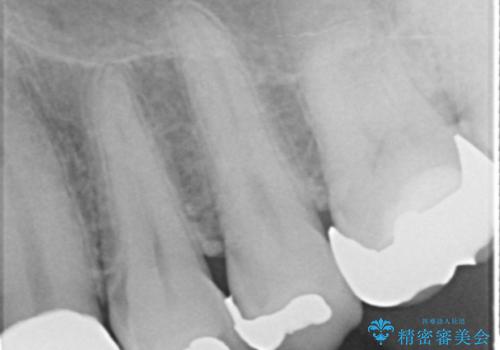

左上の側切歯(左上2)を抜去し、右上の側切歯(右上2)の再根管治療後、セラミックのブリッジによる補綴を行いました。

自然な仕上がりと咬み心地に大変ご満足頂けました。

「以前は出っ歯だったのにブリッジにしたことで歯並びもきれいになった!」と喜んで下さいました。

クラウンの種類:オールセラミッククラウン スタンダード